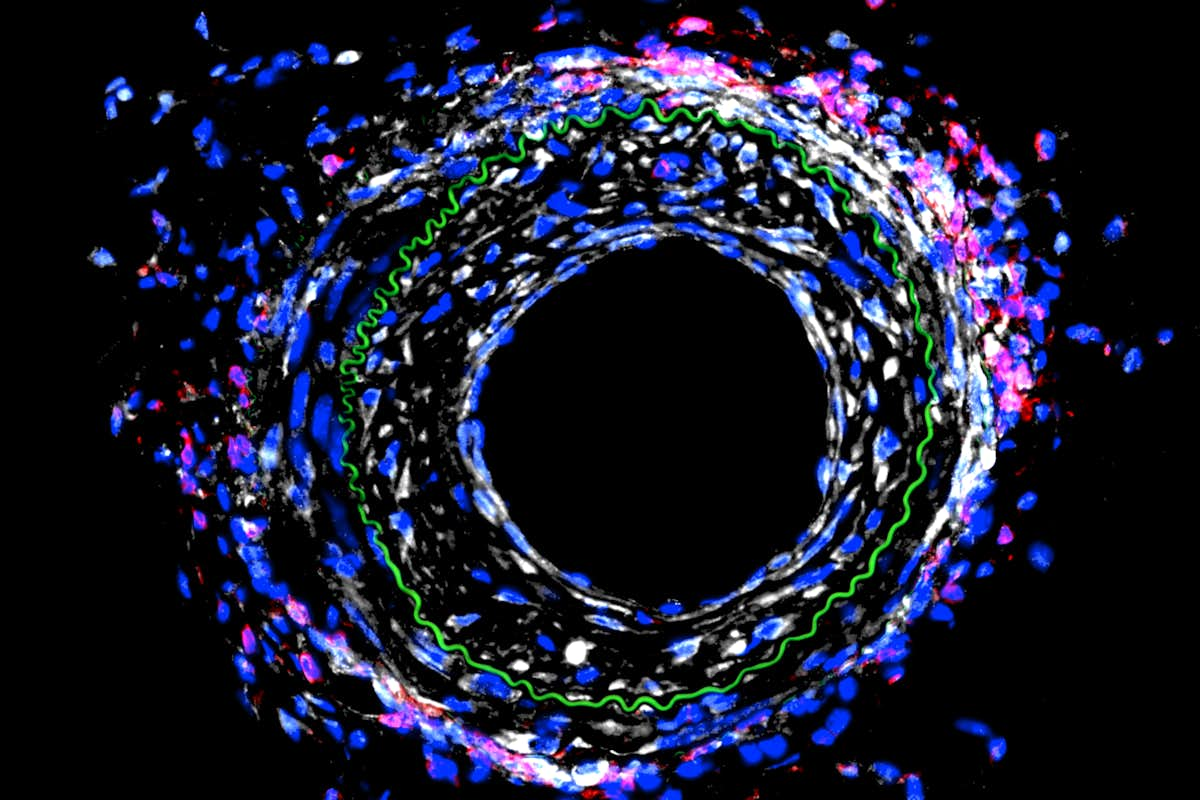

Histological image of mouse blood vessel after mechanical injury. The extent of injury is indicated by cells within the elastin layer shown in green. Cell nuclei are in blue, immune cells in red, and cadherin-11 in white. Note the localization of cadherin-11 with immune cells and its expression in the injured wall.

Heart attacks are caused by one or more blocked blood vessels, and physicians can restore blood flow in the heart with a stent or by bypassing the blockages with new vessels. A mechanical engineer at Washington University in St. Louis plans to take a closer look at how those blood vessels remodel in response to blocking a particular protein and the effect of that action on the immune system.

Matthew Bersi, assistant professor of mechanical engineering & materials science in the McKelvey School of Engineering, received a three-year, $750,000 grant from the National Institutes of Health (NIH) to study the role of the cadherin-11 protein in the mechanical injury of blood vessels after a heart attack and how cells respond to promote disease. The grant is a continuation of NIH-funded mechanobiology research he began as a postdoctoral researcher at Vanderbilt University.

Previously, Bersi found in a mouse model that blocking activity of the cadherin-11 protein after a heart attack had a beneficial effect in the heart — the heart was not as damaged as it would have been with the protein, but had a detrimental effect on the remodeling of blood vessels.

“In the early work, we found that by modulating the activity of this protein, we’re affecting the immune system, and that change in the immune system is causing the disease to be worse in the vasculature,” Bersi said. “Now, we’re investigating the mechanisms behind that to identify new directions in the treatment of this pathology. Our hypothesis is that we would alter the immune activity contributing to the disease and reduce the vessel remodeling.”